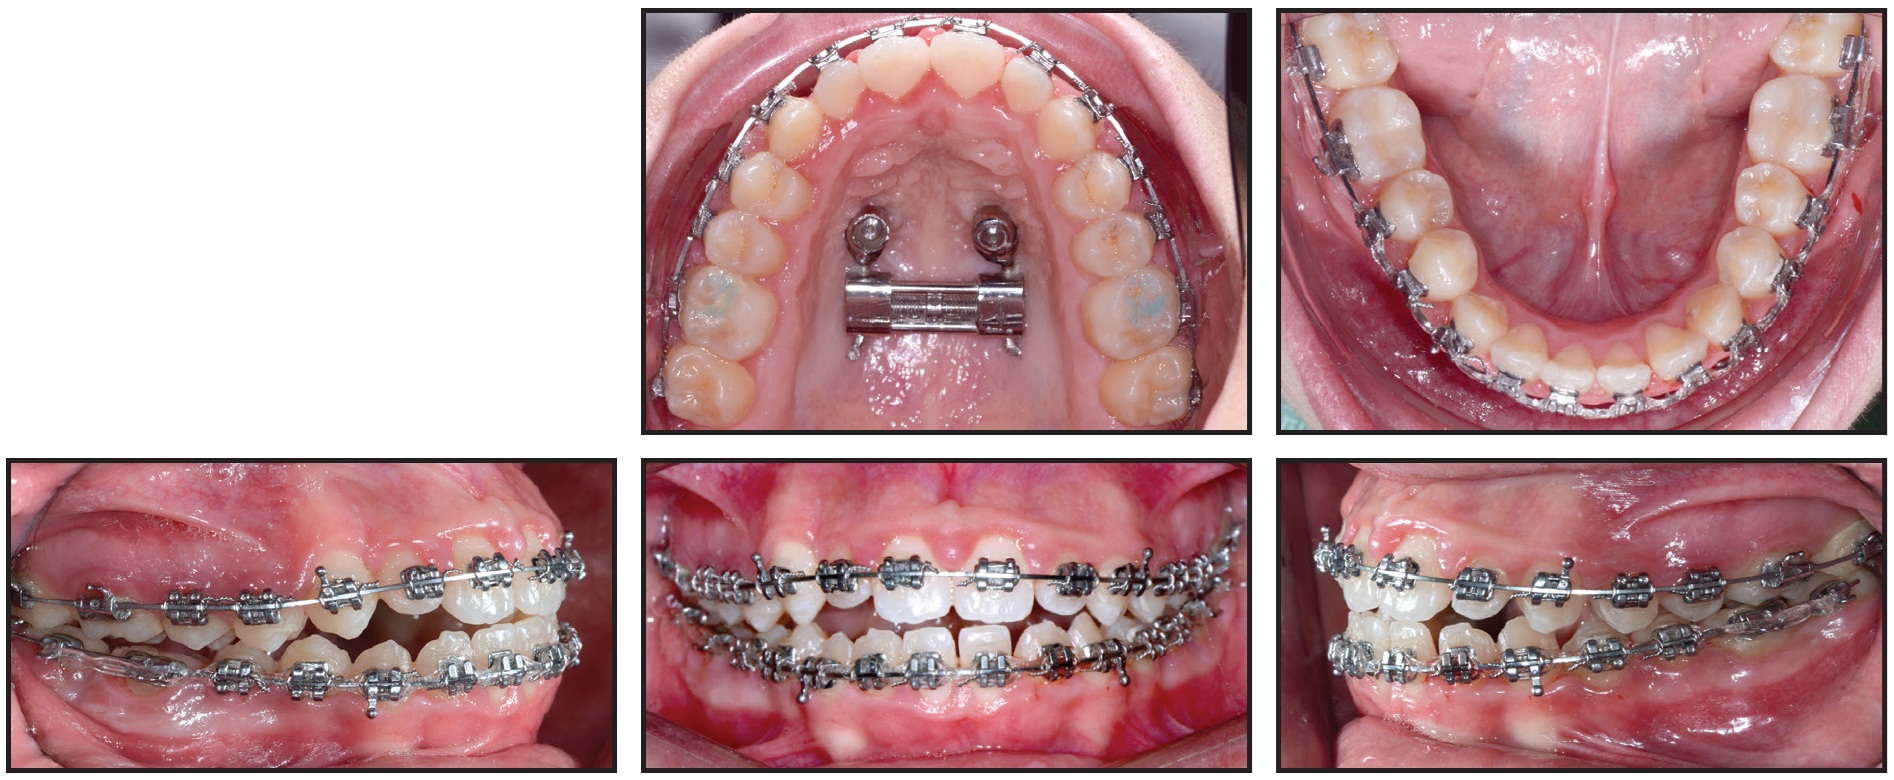

After six months of orthopedic treatment, the buccal and posterior arms of the h-RPE were removed, and the facemask was discontinued (Fig. 6).

Fig. 6 Buccal and posterior arms of h-RPE removed after six months of orthopedic treatment.

Primo** .022" labial brackets were bonded indirectly, and .014" nickel titanium archwires were inserted in both arches (Fig. 7). An open-coil spring was placed between the upper right lateral incisor and first premolar to provide space for eruption of the ectopic canine and to help center the upper dental midline.

Fig. 7 Primo** .022" labial brackets bonded and .014" nickel titanium archwires inserted in both arches; open-coil spring placed between upper right lateral incisor and first premolar to provide space for canine eruption and to center upper dental midline.